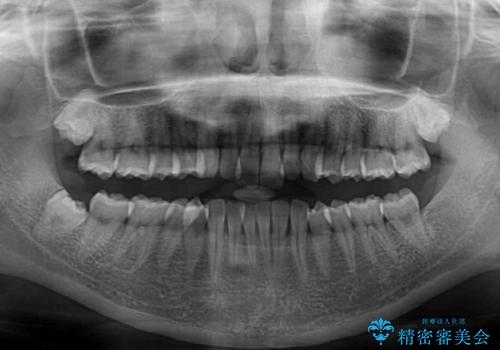

- 前歯のデコボコを気にして来院された患者様です。

全体的にデコボコが多く、特に下の前歯は隠れてしまうほどの状態でした。

左右ともに奥歯の咬み合わせが理想的な位置にあったこともあり、患者様のご希望通り、インビザラインにて矯正治療を行うこととしました。